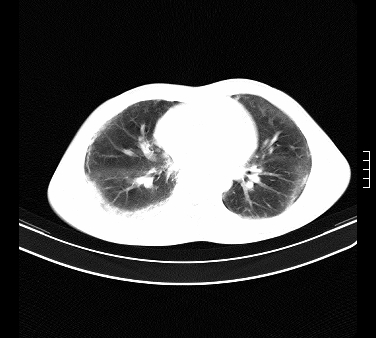

标题: CT15133:M17Y,百草枯中毒患者,典型病例分享 [打印本页]

标题: CT15133:M17Y,百草枯中毒患者,典型病例分享

患者,男,17岁,系我院急诊科收治的一例百草枯中毒患者,做ct检查时,距离服药的时间为3天。上传与大家分享

补充:百草枯进入人体内主要分部于肺和骨骼,肺部损伤24小时内出现水肿,2-3天内出现急性呼吸窘迫综合征,1-2周内出现肺纤维化。(引自陈灏珠,实用内科学12版)

不错,挺好。符合呼吸窘迫综合征